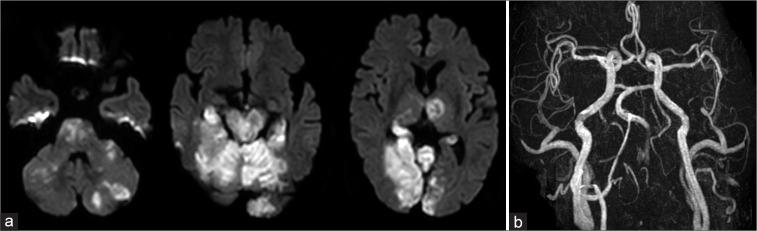

A 78-year-old man fell backward from a height of about 1 m and was rushed to his previous hospital. He had a fracture of the left transverse process of the 6 cervical vertebra. Six hours after the trauma, he became unconscious; magnetic resonance showed occlusion of the left vertebral and basilar arteries, and he was transferred to our hospital. The basilar artery was completely recanalized 430 min after the onset of unconsciousness. Due to the presence of thrombi in the distal vertebral artery at the level of the 6 cervical vertebra and collateral blood flow from the deep cervical artery, the distal vertebral artery was occluded to prevent embolism. Postoperative diffusion-weighted imaging showed extensive infarction in the posterior circulation, and the patient died two days after surgery.

In the case of vertebral artery injury, preparation for early occlusion of the basilar artery is necessary. If a thrombus and collateral blood flow are present distal to the vertebral artery injury, distal vertebral artery embolization may be necessary to prevent embolism.